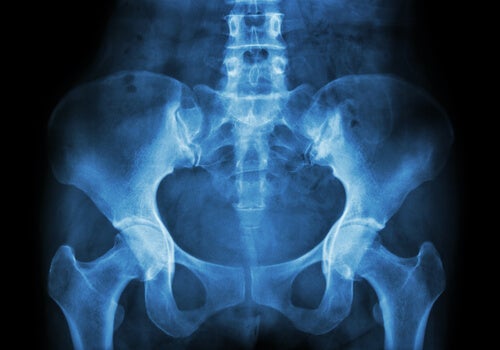

Necrosis avascular de la cadera

La necrosis avascular es un concepto utilizado para designar el infarto óseo. Lo más frecuente es que aparezca en la articulación de la cadera, en concreto en la inserción de la cabeza del fémur. Por otra parte, también puede encontrarse como necrosis aséptica, isquémica o incluso osteonecrosis.

Por otra parte, tiende a aparecer en la cabeza del fémur. Sin embargo, aparece con menos frecuencia en zonas como el húmero, la mandíbula o la tibia (en la región cercana a la rodilla).

- Obtención de imágenes internas. Se pueden realizar mediante radiografía, gammagrafía ósea, resonancia magnética (o RM), tomografía axial computerizada (o TAC).